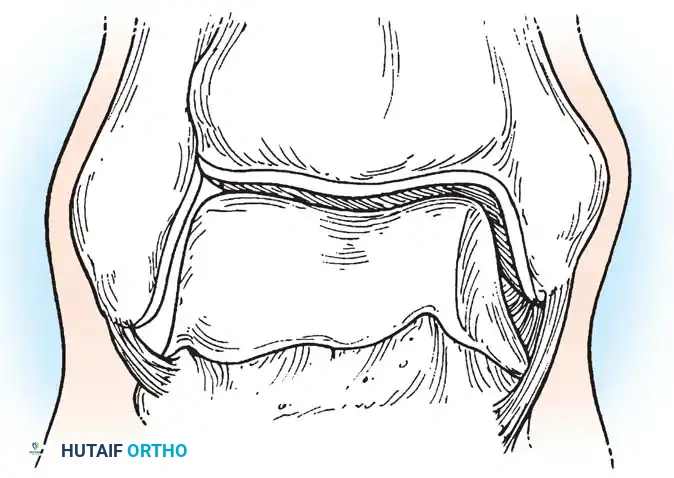

4. The Systematic Diagnostic Tour

Any arthroscopic procedure must begin with a thorough, reproducible, systematic examination of the joint to ensure no concomitant pathology is overlooked. The ankle is conceptually divided into anterior and posterior compartments, each further subdivided into medial, central, and lateral zones.

The Anterior Compartment Sweep:

* Anteromedial Zone: Visualize the deep portion of the deltoid ligament, the medial talomalleolar articulation, and the medial tibiotalar joint. Look for medial gutter synovitis or osteophytes.

* Central Zone: Sweep across the dome of the talus and the corresponding tibial plafond. Probe the cartilage for softening, fibrillation, or frank osteochondral defects. Dynamic plantarflexion and dorsiflexion under traction significantly improve exposure of the talar dome.

* Anterolateral Zone: Examine the lateral tibial plafond, the lateral talomalleolar articulation, and the intra-articular portion of the anterior talofibular ligament (ATFL).

* Anterior Gutter: Sweep the scope distally over the talar neck. Inspect the anterior lip of the tibia for impingement osteophytes (often seen in athletes) and thoroughly check the anterior gutter for hidden loose bodies.

The Posterior Compartment Sweep:

In ankles with adequate ligamentous laxity or sufficient non-invasive distraction, the posterior compartment can be viewed from the anterior portals.

* Evaluate the posteromedial, central, and lateral tibiotalar articulations.

* Inspect the posteroinferior tibiofibular ligament and the transverse ligament.

* Loose Body Hunt: Loose bodies frequently migrate and become entrapped posterior to the tibiofibular ligaments. The surgeon should manually massage the posterior soft tissues of the ankle to express potential loose bodies into the arthroscopic field of view.